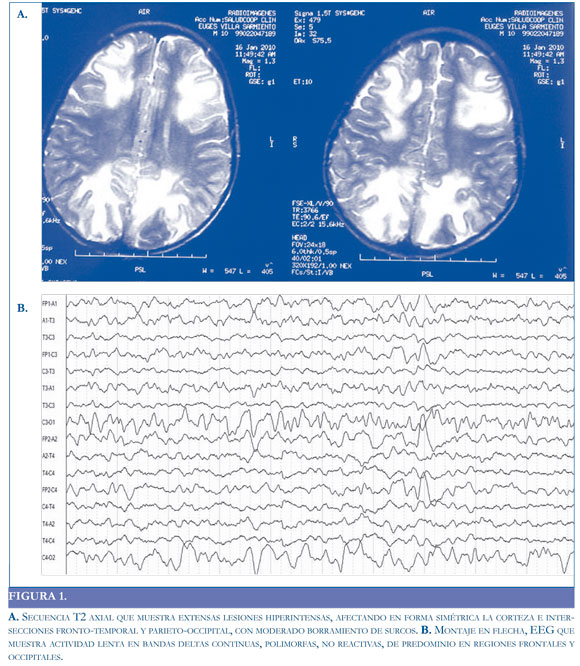

Por mejoría de los síntomas, se trasladó a sala de hospitalización, donde se inició manejo sintomático, se encontró mejoría de la fuerza en hemicuerpo izquierdo y no volvió a presentar episodios convulsivos. Se encontró desaparición del edema en la RM y el EEG mostró desaparicion de las ondas lentas y mejor organización de la actividad eléctrica cerebral (Figura 2).

Algunos autores sugieren que si el compromiso es cortical (sustancia gris), predomina la actividad delta polimorfa y si el compromiso es subcortical, los patrones arrítmicos son más comunes. Por lo general, la severidad del cuadro clínico se corresponde con las anormalidades registradas en el EEG (19). En el caso presentado, el EEG en la etapa aguda de la enfermedad mostró un ritmo de fondo delta, polimorfo, difuso (bilateral), no reactivo que se fue organizando en la medida en que el paciente fue mejorando clínicamente.

En este caso se evidencia la utilidad de ambos estudios en el diagnóstico y evolución clínica de la encefalopatía; debido a que su normalización se correlaciona con la mejoría de la sintomatología, sugerimos que estos estudios (Resonancia Magnética y electroencefalograma) deben practicarse en forma seriada a este tipo de pacientes.